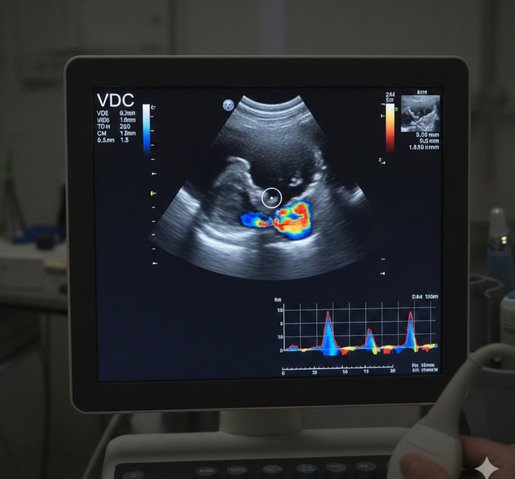

Ecografía Doppler VDC

La ecografía Doppler de vasos de cuello es un estudio no invasivo que permite evaluar las arterias carótidas y vertebrales, analizando su anatomía y el flujo sanguíneo cerebral. Este estudio es fundamental para la detección y el seguimiento de alteraciones vasculares, como estenosis, placas ateromatosas o cambios en la circulación, especialmente en pacientes con factores de riesgo cardiovascular.